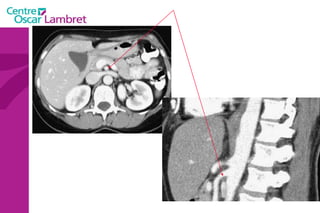

L’appareil urinaire L’appareil urinaire se compose des reins, des uretères et de la vessie. Les reins  sont rétro-péritonéaux : de part et d’autre du rachis entre T12 et L3. Fixés sous les côtes, ils sont en liaison avec l’artère rénale . Le rein possède une fonction secrétoire puis excrétoire à partir du pyelon, origine de l’uretère.

L’appareil urinaire

L’appareil urinaire Les uretères  se dirigent vers le bas, en avant et en dedans pour rejoindre la partie postéro supérieure de la vessie. On distingue 3 parties : L’uretère lombaire (12 cm) L’uretère iliaque (3 cm) L’uretère pelvienne (12 cm)

La vessie  : Elle recueille l’urine qui lui parvient par les uretères. L’urine est évacuée par l’urètre lors de la miction. L’appareil urinaire

Les surrénales  sont 2 glandes endocrines triangulaires situées au dessus des reins. Elles sont principalement responsables de la gestion des situations de stress via la synthèse de corticostéroïdes et de cathécolamines, entre autres le cortisol et l‘adrénaline.  Intérêt d’un balisage digestif pour l’étude de ces glandes L’appareil urinaire